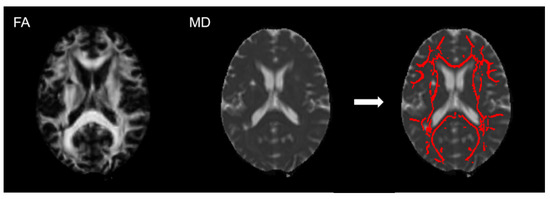

2.4. Imaging Analysis